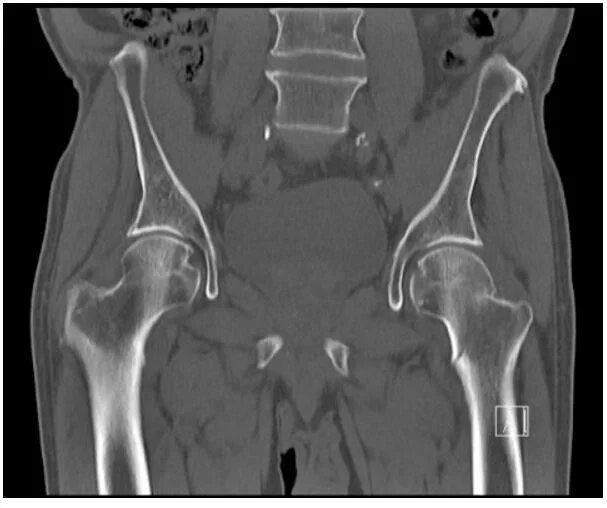

Кт суставов что показывает